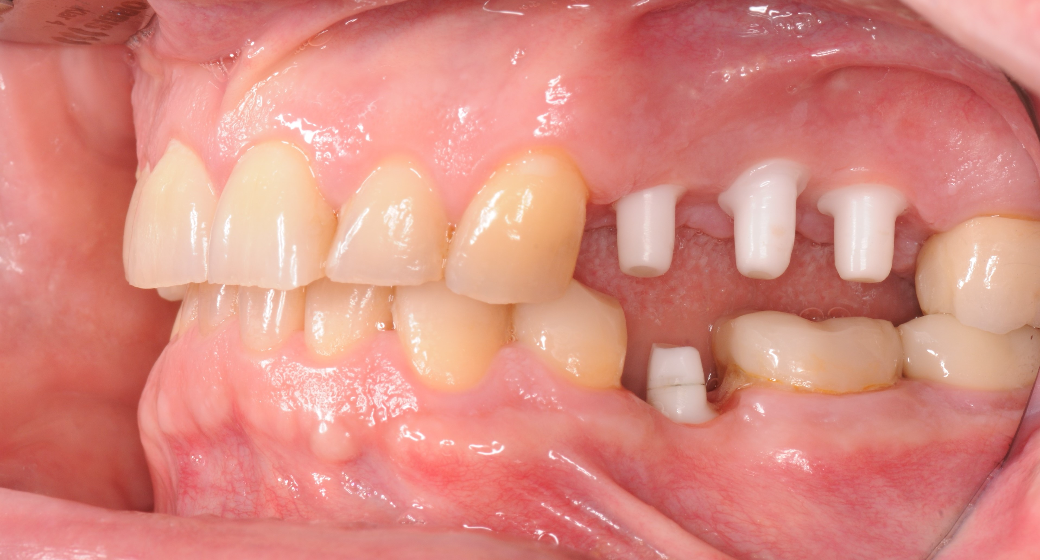

Behandlung Vorher-Nachher-Bild | Implantate  | von Dr. med. dent.  Gero  Böthig  | Bernried am Starnberger See d9d4f495 Vorher-Bild

Vorher

Alle durchgeführten Behandlungen bei diesem Fall: Implantate

24 Z.n. Endo + Krone - 25 Brückenglied - 26 Brückenglied - 27 Krone; 35 fehlt

Entfernung 24 + keramisches Sofortimplantat - 25 Keramikimplantat - 26 Keramikimplantat + interner Sinuslift; 35 Keramikimplantat Alle Implantate wurden mit Zirkonkronen versorgt.

männlich, 56 Jahre